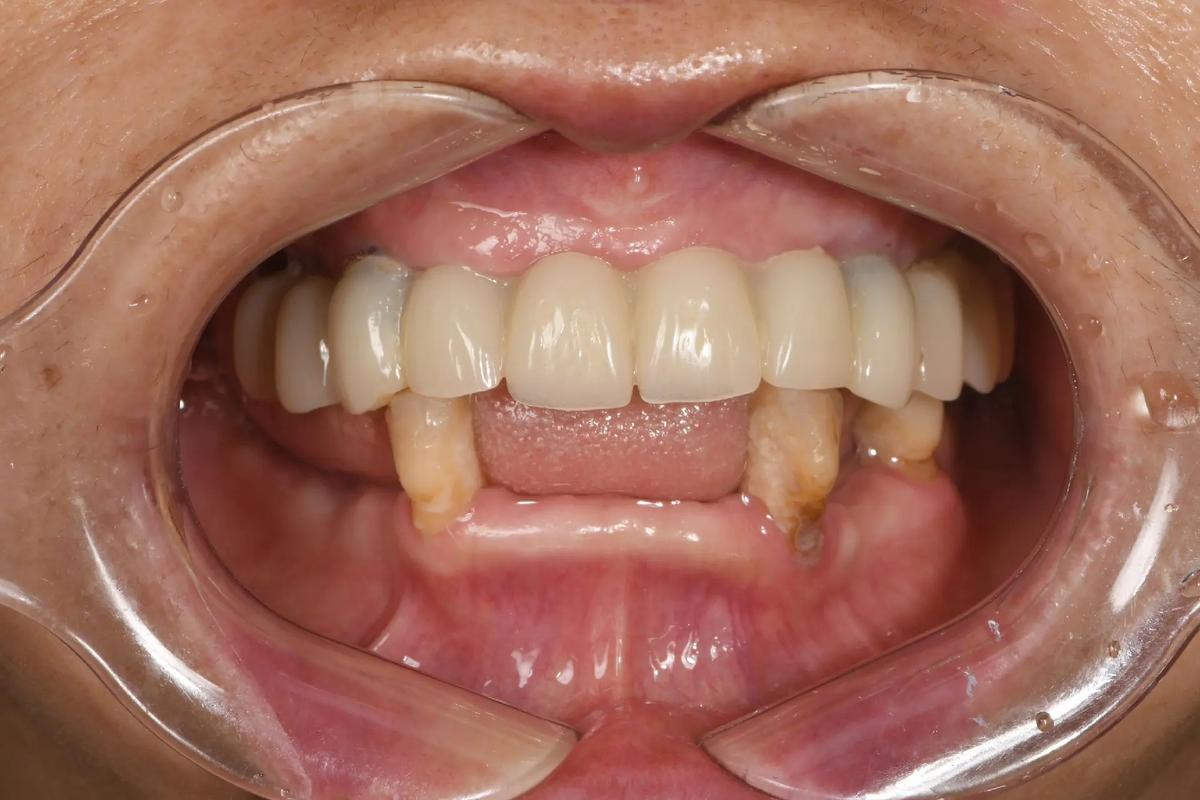

- 美观和功能恢复更快(尤其对于即刻负重):如果条件允许(种植体初期稳定性好、骨质量好),可以在种植体植入后当天或短期内(几天内) 就安装临时牙冠(即刻负重),实现快速恢复部分咀嚼功能和美观。

- 并非“当天戴牙”:虽然叫“急种”,但“即刻负重”是更高阶的要求,需要更严格的条件(如良好的初期稳定性、良好的骨质量、非功能区域或咬合力小的区域),大多数“急拔急种”指的是即刻植入种植体,但最终修复(戴永久牙冠) 仍然需要等待数月(通常3-6个月)以确保骨结合完成。“即刻负重”是“急种”中的特殊情况。